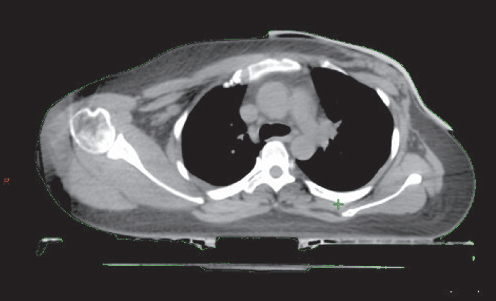

新技术注入新活力,新起点迎来新发展。近日,乳腺放疗病区将3D打印技术与放疗技术相结合,成功实施3D打印硅胶组织补偿物新技术,有效提高了放疗剂量稳定性,为患者提供了精准化、个体化治疗。 乳腺放疗病区实施3D打印组织补偿物技术实例 常规组织补偿物与体表的空气间隙 由于人体体表是不平坦的曲面,且因术后瘢痕的形成,表面为平面的常规组织补偿物与皮肤之间不能完全贴合,必然存在空气间隙。空气间隙使浅表组织的实际受照剂量存在较大的不确定性,靶区剂量分布与放疗计划存在不符,影响放疗疗效。 3D打印组织补偿物制作技术示意图 为解决该问题,乳腺放疗病区将3D打印与放疗技术相结合,实施了3D打印硅胶组织补偿物的新技术。3D打印组织补偿物是应用3D打印技术,基于每位患者体表曲度数据,使用质地均一、电子密度接近于水、制作时间短、易于成型的硅胶材料制作的组织补偿物。“量身定制”的3D打印组织补偿物具有个体化程度高、与患者体表贴合程度高等明显的优势,且其同时具有硅胶材料的均匀性、适形性、生物等效性和可重复性,因此能够有效提高放疗剂量的准确性及稳定性。 3D打印组织补偿物与体表的空气间隙明显缩小 3D打印组织补偿物的应用为目前国内外领先技术。今后,乳腺放疗病区将继续对先进的新技术领域不断探索,致力于最大程度体现乳腺癌精确放疗理念,实现最优的医疗质量。